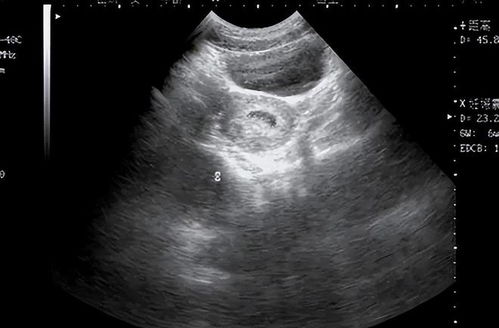

在孕期,B超检查是监测胎儿发育状况的重要手段之一。特别是在24周左右,进行系统B超检查对于了解胎儿的整体健康状况和发育情况具有重要意义。

在发现异常情况后,孕妇应保持冷静,按照医生的建议进行相应的检查和治疗。